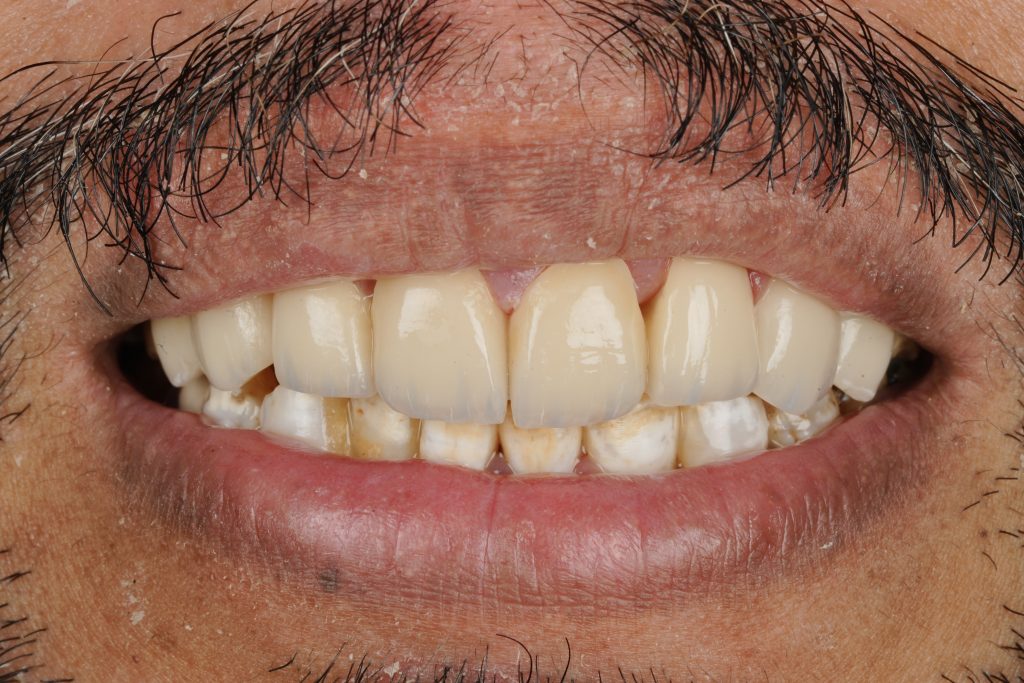

Each veneer was etched with 9 % HF acid for 20 seconds, silanated, and dried. Teeth were treated with 37 % phosphoric acid and universal adhesive (Clearfil Universal Bond Quick). Light-cure resin cement (Variolink Esthetic LC) was applied under full-arch rubber-dam isolation. Excess cement was removed and polymerization performed for 40 s per surface (Fig 4).

Margins were refined using fine diamond strips, and surface gloss was enhanced with a multi-step polishing system (Shofu OneGloss + OptraPol Next Gen). Post-operative evaluation showed ideal incisal translucency, line-angle symmetry, and gingival health (Fig 5 & 6).